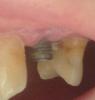

Stacy Опубликовано 18 октября, 2013 Поделиться Опубликовано 18 октября, 2013 (изменено) Подскажите пожалуйста!!!! Это совсем печально??? К стоматологу могу попасть только через 2 недели... Был установлен имплант 29 августа... Все было нормально,никаких осложнений.... А сейчас вот так это выглядит... Один нормально не вылез.. А второй вот такая картина.... Изменено 18 октября, 2013 пользователем Stacy Ссылка на комментарий

Bier Опубликовано 19 октября, 2013 Поделиться Опубликовано 19 октября, 2013 да он сам уже удалился. 2 Ссылка на комментарий

red_butler Опубликовано 19 октября, 2013 Поделиться Опубликовано 19 октября, 2013 Если не удалить - выпадет сам. Обратитесь к оперировавшему хирургу. Ссылка на комментарий